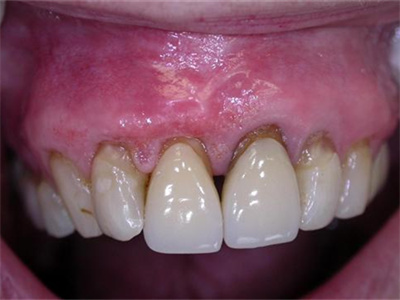

牙龈炎是发生于牙龈组织的炎症,患者可出现牙龈出血伴肿胀、发红、正常形态改变和偶尔不适等症状。本病主要由口腔卫生状况差导致,包括口腔不洁、牙菌斑等,诊断依据临床检查,治疗包括专业牙齿清洁和加强家庭口腔卫生。

牙龈炎可先引起牙齿与牙龈之间的沟(龈沟)加深,然后牙龈充血,炎症围绕一个或多个牙齿,伴牙龈乳头肿胀和易出血。一般无痛,可自行消退,也可维持轻度炎症数年。

牙龈炎患者可通过改善口腔卫生控制疾病,同时使用抗菌漱口液,如复方氯己定含漱液,并进行彻底的洁治处理。必要时,重新修整修复体的不良外形,并祛除局部刺激因素。